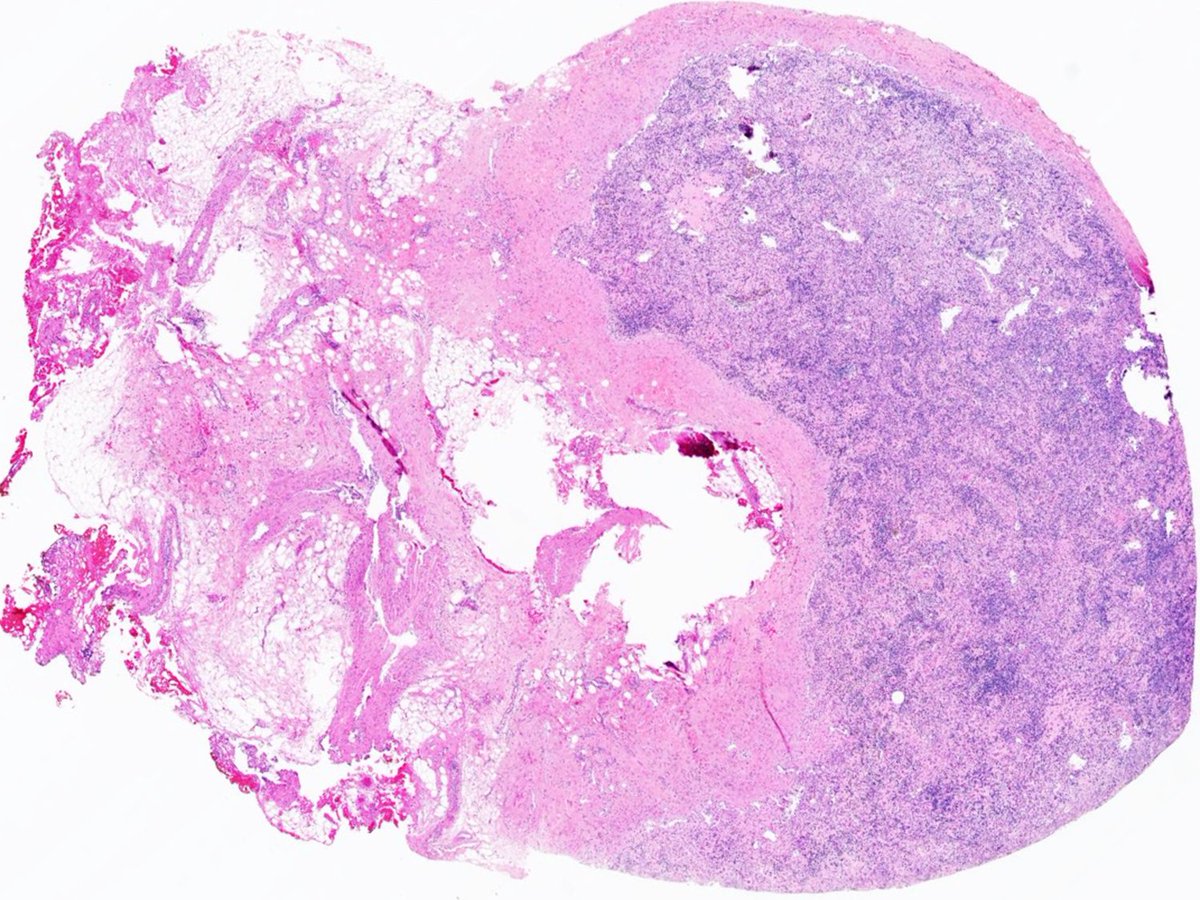

Example of a case of "Diffuse large B-cell lymphoma associated with chronic inflammation", developing in the pleural cavity of a patient with longstanding pyothorax➡️ #Hemepath #PathX #Pathtwitter #MedX #MedTwitter #Surgpath #SoMe